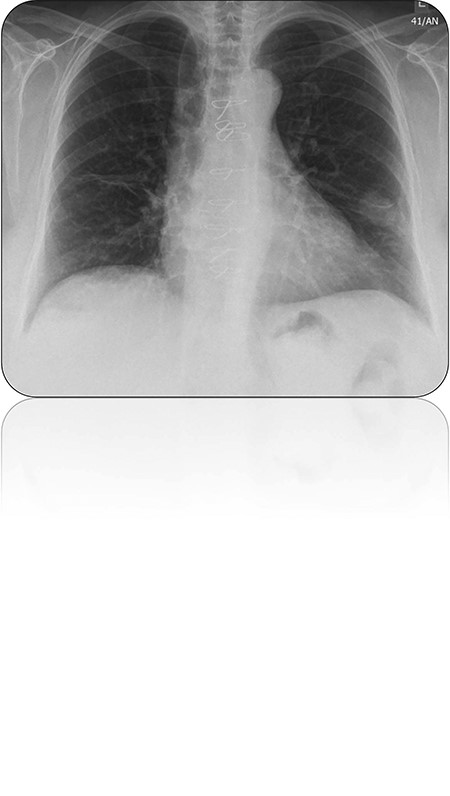

We describe a case of a middle-aged female diagnosed with synchronous primary lung and breast cancers. A history of recurrent chest infections resulted in the request of a routine chest X-ray. This subsequently demonstrated a nodule within the left lower lobe (Fig. 1). Computer tomography (CT) of the thorax demonstrated a mass within the left lower lobe as well as enlarged axillary lymph nodes. Previous mammography and magnetic resonance imaging had failed to demonstrate any lesions within the left breast. The aforementioned was further evaluated by positron emission tomography with CT, which demonstrated the lung lesion and lymph nodes to be metabolically active. Comorbidities included an aortic valve bioprosthesis, osteoarthritis, fibromyalgia and multiple gynaecological operative procedures. Biopsy of an axillary lymph node proved to be of breast origin. A CT-guided biopsy of the lung lesion demonstrated it to be of primary lung origin. This case was discussed at the multidisciplinary meeting and it was decided that this patient is a candidate for surgery to remove both lesions. This patient was subsequently brought forth for concomitant surgery to remove both the breast and lung lesions. Initially patient underwent a left mastectomy (Fig. 2) and left axillary node clearance. Attention was then directed towards completing a left lower lobectomy via an anterolateral thoracotomy through the same mastectomy incision with the patient supine but tilted towards the right (Fig. 3). Post-operative recovery was essentially unremarkable and the patient was discharged 1 week following her procedure. Histology was consistent with both primary adenocarcinoma of the lung and metastatic breast carcinoma within the lymph nodes and a ductal carcinoma in situ arising from the left breast (Fig. 4). The patient was subsequently referred for further oncological therapy.